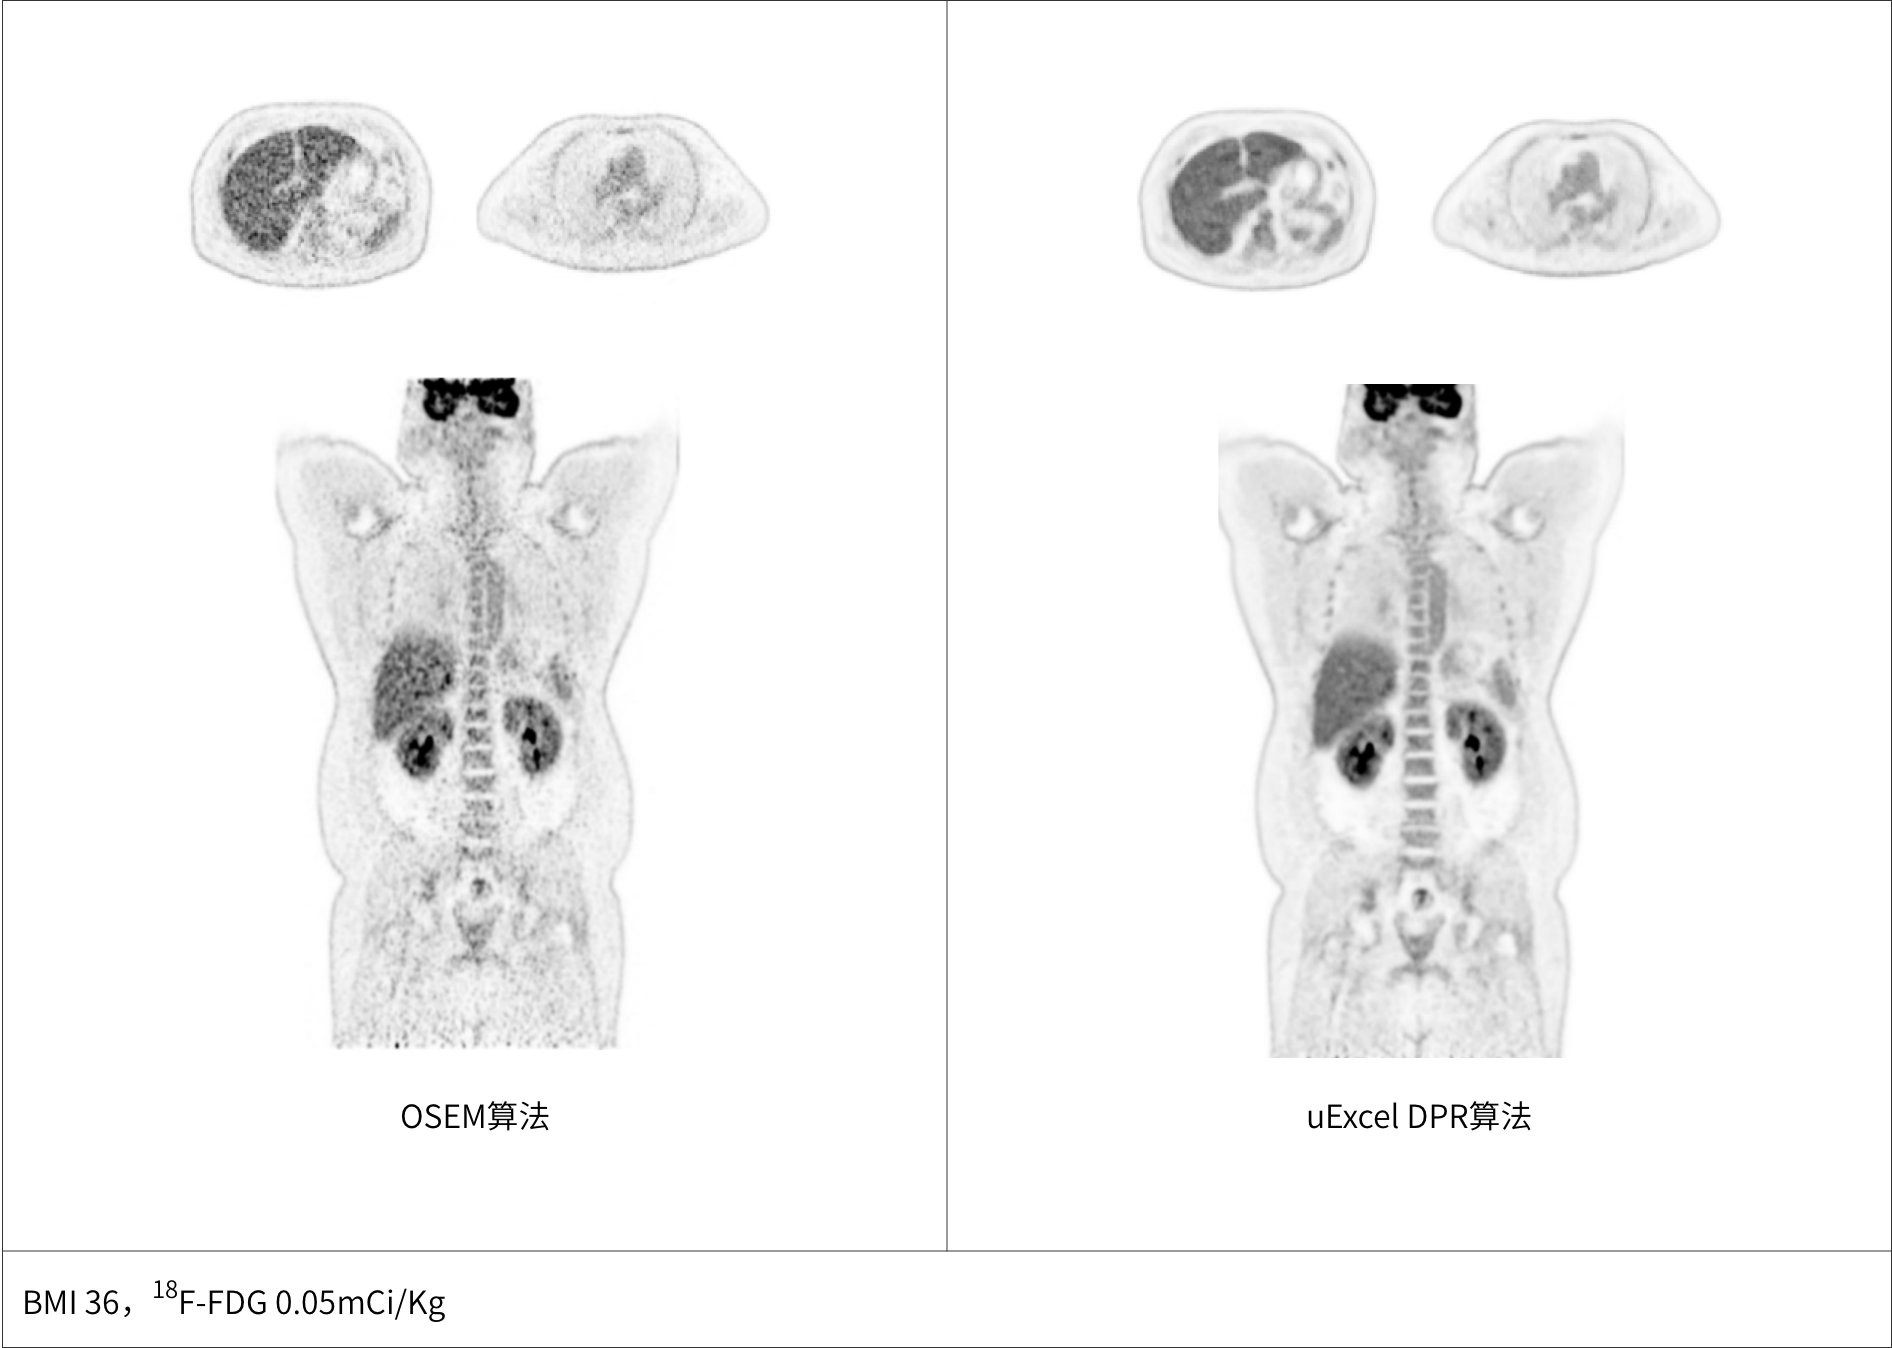

uExcel DPR*全面优化PET-CT扫描条件

兼顾噪声、对比度、分辨率等多维度进行分布渐进式学习优化

极低噪声、高对比度uEXPLORER海量优质图像训练集有效保证输出结果的可靠性

PET图像全维优化

同时实现图像对比度、噪声、信噪比三重优化

*uExcel DPR仅供科研使用

大体重患者主动脉血管结构清晰显示